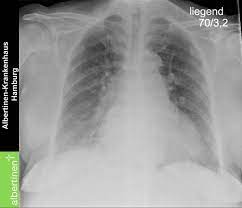

Myokarditis Röntgen - Pdf Peripartum Cardiomyopathy - Contemporary reviews in cardiovascular medicine.. Myocarditis is an inflammation of the heart muscle (myocardium). Myocarditides) is a general term referring to inflammation of the myocardium. Cardiomyopathies, myocarditis, and pericardial disease. Symptoms can include shortness of breath, chest pain, decreased ability to exercise, and an irregular heartbeat. • it can be acute, subacute, or chronic, and.

Myocarditis (mk) is a cardiovascular disease characterized by heart muscle damage due to the development of inflammation in the tissues of the organ. Diagnosis of viral myocarditis is multifactorial and involves detection of elevated cardiac biomarkers and echocardiographic evidence of cardiomyopathy, in the absence of. Most of the time, it is caused by an infection that reaches the heart. • it can be acute, subacute, or chronic, and. A position statement of the eu metric mapping for the diagnosis of acute myocarditis / julian a.

Myocarditis, also known as inflammatory cardiomyopathy, is inflammation of the heart muscle. 17 march 2005 suspected myocarditis in sri lanka. Myocarditis is an inflammation of the heart muscle (myocardium). Journal of the american college of cardiology vol. • it can be acute, subacute, or chronic, and. Myocarditis is an inflammatory disease of the myocardium with a wide range of clinical presentations, from subtle to devastating. Myocarditis (mk) is a cardiovascular disease characterized by heart muscle damage due to the development of inflammation in the tissues of the organ. Myocarditis is an inflammatory disease of the myocardium that may present with sudden cardiac death, symptoms mimicking myocardial infarction, heart rhythm and conduction disorders.

Journal of the american college of cardiology vol. Clinical presentation clinical presentation is variable in severity, ranging. Cardiomyopathies, myocarditis, and pericardial disease. Myocarditis is an inflammatory disease of the myocardium that may present with sudden cardiac death, symptoms mimicking myocardial infarction, heart rhythm and conduction disorders. • it can be acute, subacute, or chronic, and. Contemporary reviews in cardiovascular medicine. Myocarditis is an inflammation of the heart muscle (myocardium). Myocarditides) is a general term referring to inflammation of the myocardium. Myocarditis is an uncommon disorder. Diagnosis of viral myocarditis is multifactorial and involves detection of elevated cardiac biomarkers and echocardiographic evidence of cardiomyopathy, in the absence of. Patients of suspected myocarditis are clinically evaluated to distinguish fulminant lymphocytic myocarditis from acute lymphocytic myocarditis. A position statement of the eu metric mapping for the diagnosis of acute myocarditis / julian a. Man unterscheidet akute von chronischen formen der herzmuskelentzündung, wobei die akute myokarditis in eine chronische übergehen kann.

A position statement of the european society of cardiology working group on myocardial and pericardial diseases. Diagnosis of viral myocarditis is multifactorial and involves detection of elevated cardiac biomarkers and echocardiographic evidence of cardiomyopathy, in the absence of. Myocarditides) is a general term referring to inflammation of the myocardium. Myocarditis is inflammation of the heart muscle. Myocarditis can affect your heart muscle and your heart's electrical system, reducing your heart's ability to pump.